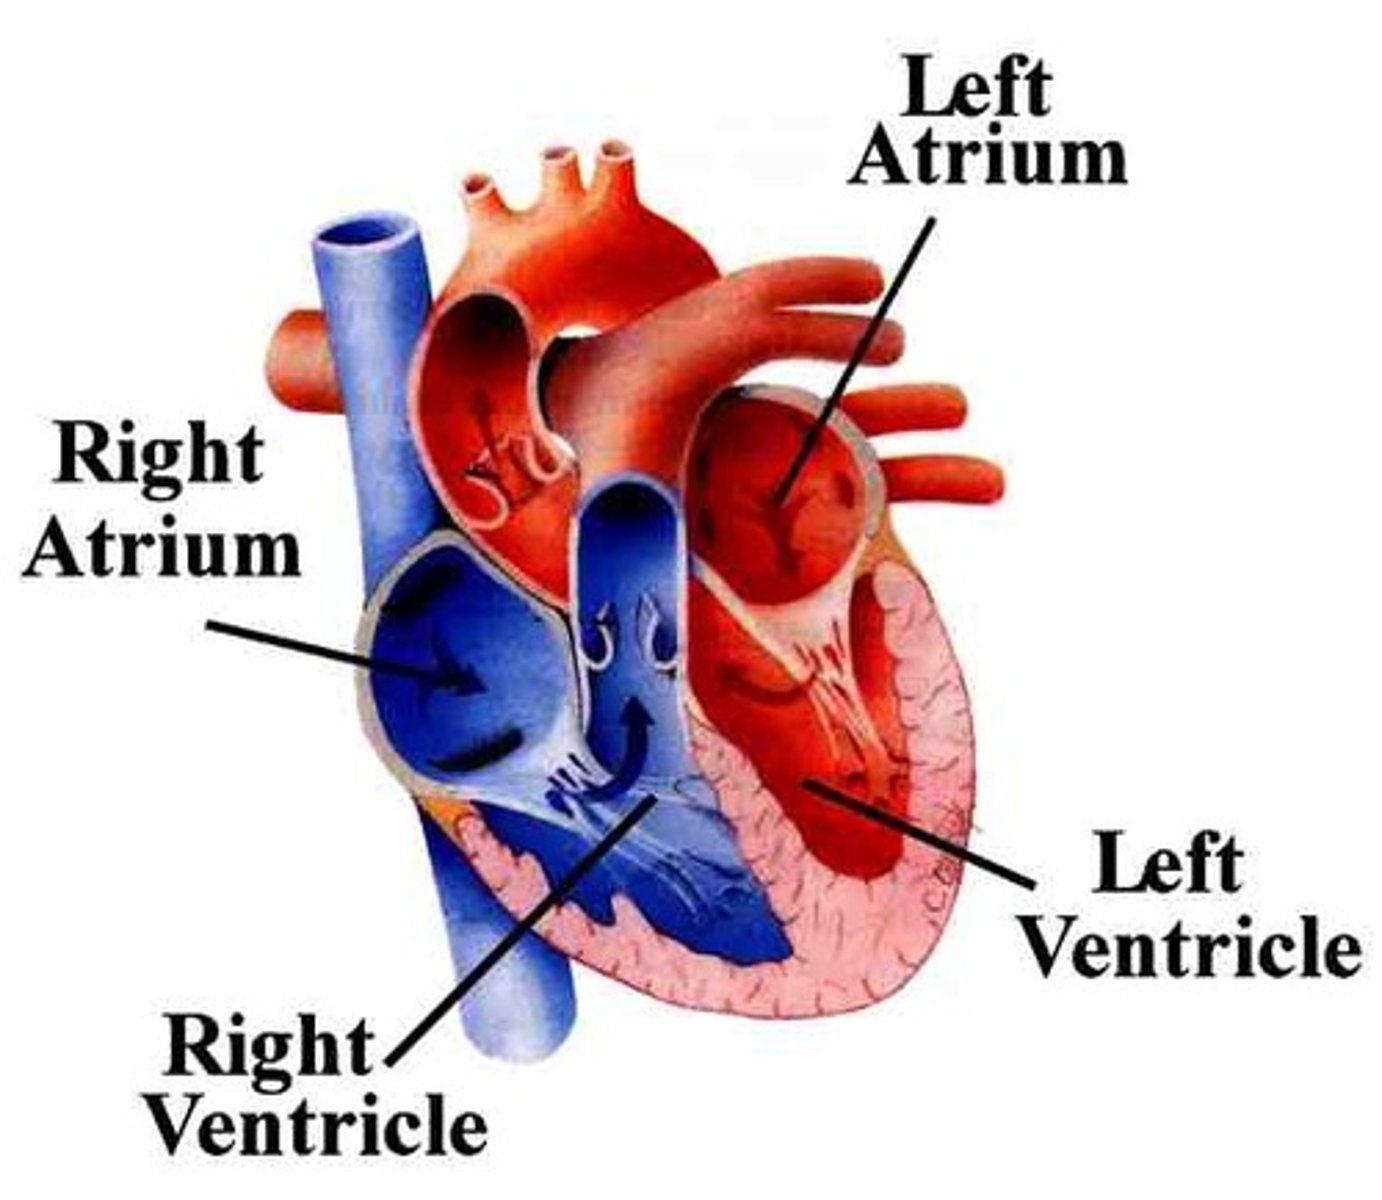

Two atria; right and left (receiving chambers)

Two ventricles; right and left (discharging chambers)

Name the four chambers

The right atrium receives deoxygenated blood from:

The four pulmonary veins (right superior, right inferior, left superior, left inferior)

The left atrium receives oxygenated blood from:

From: Left atrium through the bicuspid valve

To: Aorta through semilunar valve to systemic system

The left ventricle receives blood from:

and sends it:

From: Right atrium through tricuspid valve

To: Pulmonary trunk (artery) through semilunar valve to lungs then pulmonary veins

The right ventricle receives blood from:

and sends it: